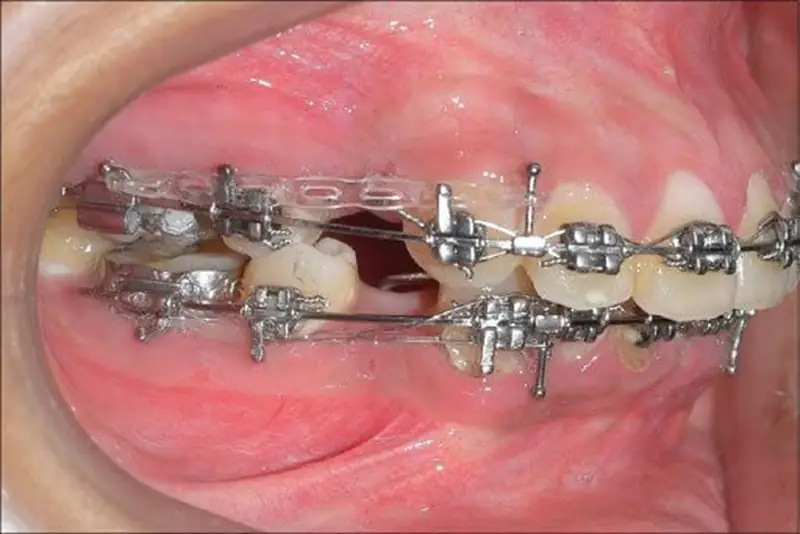

Trong chỉnh nha, đóng khoảng là quá trình bác sĩ sử dụng lực kéo từ dây cung, lò xo hoặc thun chỉnh nha để di chuyển các răng lại gần nhau, lấp đầy khoảng trống trên cung hàm. Những khoảng trống này thường được tạo ra có chủ đích trong kế hoạch điều trị, giúp răng có không gian dịch chuyển chính xác hơn. Nhờ đó, các răng sẽ dần sắp xếp đúng vị trí trên cung hàm. Đây là bước quan trọng để hoàn thiện cấu trúc răng và chuẩn bị cho giai đoạn tinh chỉnh khớp cắn.

Trong nhiều trường hợp răng chen chúc hoặc hô, bác sĩ có thể chỉ định nhổ răng để tạo khoảng trống cần thiết trên cung hàm. Những chiếc răng thường được nhổ là răng số 4 hoặc răng số 5 nhằm tạo không gian cho các răng khác dịch chuyển. Khoảng trống sau khi nhổ răng sẽ được lấp đầy dần trong giai đoạn đóng khoảng. Nhờ vậy, toàn bộ hàm răng có thể sắp xếp cân đối hơn mà không gây chồng chéo.

Giai đoạn đóng khoảng được xem là một bước then chốt trong kế hoạch chỉnh nha. Đây là thời điểm các khoảng trống trên cung hàm dần được lấp đầy nhờ lực kéo từ hệ thống mắc cài, dây cung hoặc thun chỉnh nha. Khi các răng di chuyển đúng hướng và đúng vị trí, cấu trúc cung hàm sẽ trở nên cân đối và ổn định hơn. Điều này tạo nền tảng quan trọng để quá trình niềng răng đạt được kết quả tối ưu.

Nếu giai đoạn đóng khoảng được thực hiện đúng kỹ thuật, răng sẽ dịch chuyển từ từ, ổn định và hạn chế tối đa các biến chứng không mong muốn. Nhờ đó, các bước tiếp theo như tinh chỉnh khớp cắn và điều chỉnh chi tiết vị trí răng sẽ diễn ra thuận lợi hơn. Ngược lại, nếu lực kéo không được kiểm soát tốt, răng có thể di chuyển sai hướng hoặc mất nhiều thời gian để điều chỉnh lại. Điều này có thể khiến tổng thời gian niềng răng kéo dài hơn so với kế hoạch ban đầu.